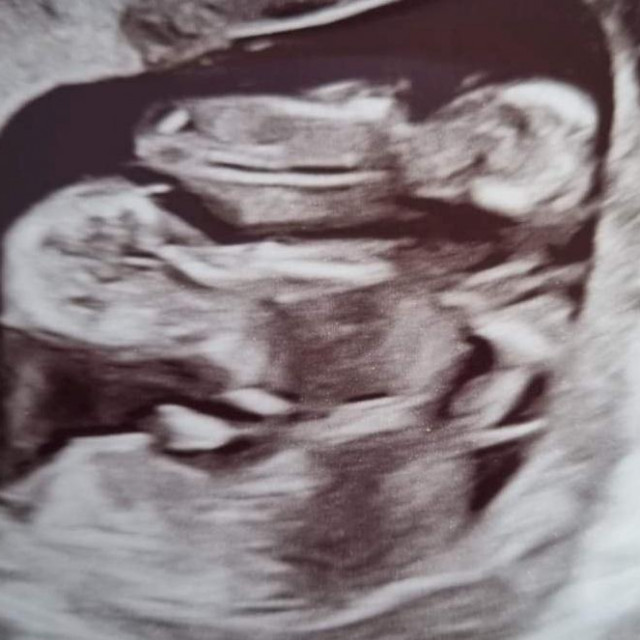

I LIJEČNICI U ČUDU Na pregledu joj otkrili da ima dvije maternice, a onda je uslijedio još već šok: ‘Šanse su jedan prema milijun!‘ 16.11.2023. u 18:35